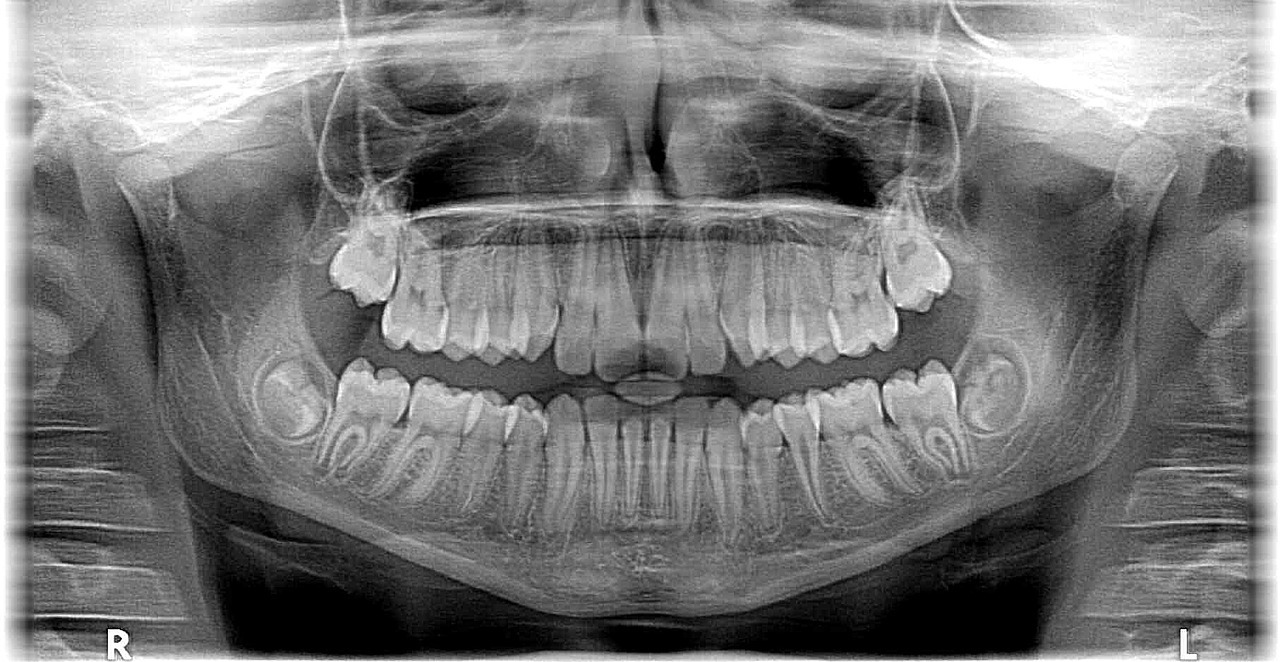

사랑니란 치아 중 가장 안쪽에 위치해 있습니다. 사랑니는 입안에서 가장 늦게 자라나는 치아로 사랑을 경험하는 나이쯔음에 생긴다고해서 사랑니라고 불린다고 합니다. 전문의학 용어로는 제 3대 구치 또는 지치라고 불립니다. 얼굴의 중심, 가운데 앞니 기준으로 좌우로 8번째 자리에 있다고 합니다.

유치에는 존재하지 않고, 영구치가 나기 시작하고도 한참후에 나온다고 합니다. 평균적으로 17~20세쯤 맹출하는데 60세 맹출하는 사람도 있다고 합니다. 선천적으로 없거나 일부 1~3개만 나는 사람도 있다고 합니다.

위 사진은 실제로 제 치아사진입니다. 윗 사랑니들은 나름 일자로 잘 나있으나 사진으로 왼쪽치아는 누워있는게 보이시죠? 이렇게 누워있으면 옆에 어금니 치아를 밀어내서 치열이 엉망이 된다고 합니다. 그래서 뽑아주는게 좋다고 합니다.